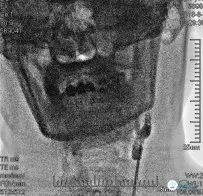

头颈CTA(2018-05-16):左侧颈内动脉闭塞(图2)

头部CTA(2018-06-08):左侧颈内动脉未见显示,走行区可见多发钙化;右侧颈内动脉岩骨段、海绵窦段管壁可见钙化,管腔多发狭窄。右侧大脑前动脉水平段纤细。左侧大脑中动脉显示纤细。左侧后交通动脉未见明确显示(图3)

颈部高分辨磁共振(2018-06-13):双侧颈总动脉分叉部管壁略厚;左侧颈内动脉起始处以远闭塞(图6)